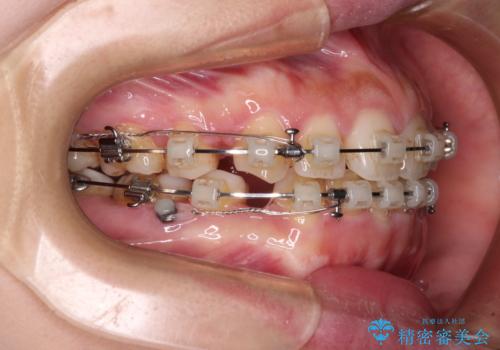

- 矯正装置

- クリアブラケット

- 治療期間

- 3年

- 治療回数

- 30回以上